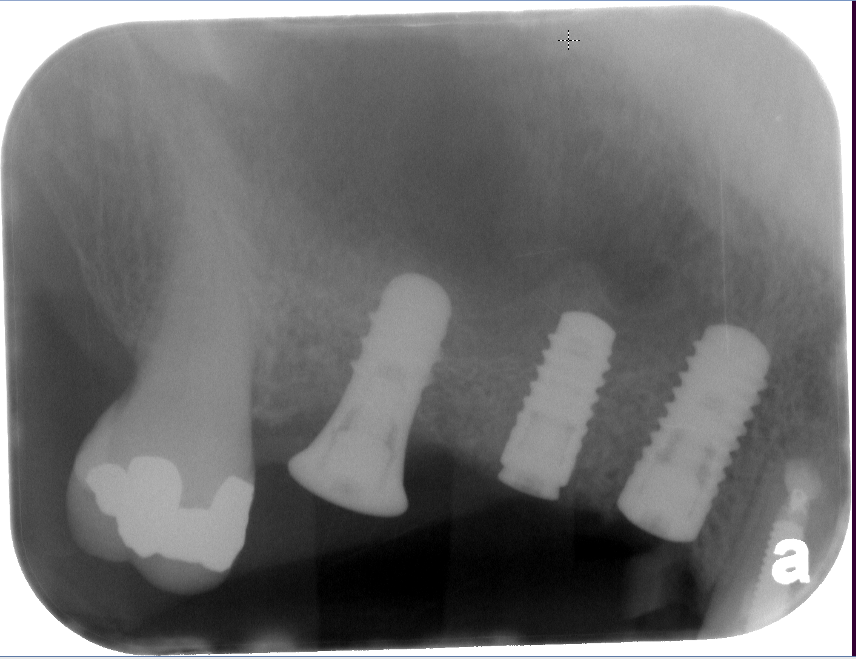

Sinus Lift Implant Vancouver Burnaby Periodontist Implant Dentist IMPreESS Perio

Dental Implant Centre in Vancouver Burnaby Sinus Lift Dental implant Surgery Dr. Noroozi Implant Specialist IMPrESS Perio Implant Center.001

Sinus Lift, Bone Graft, Implants Dr. Noroozi IMPrESS Perio Implant Center